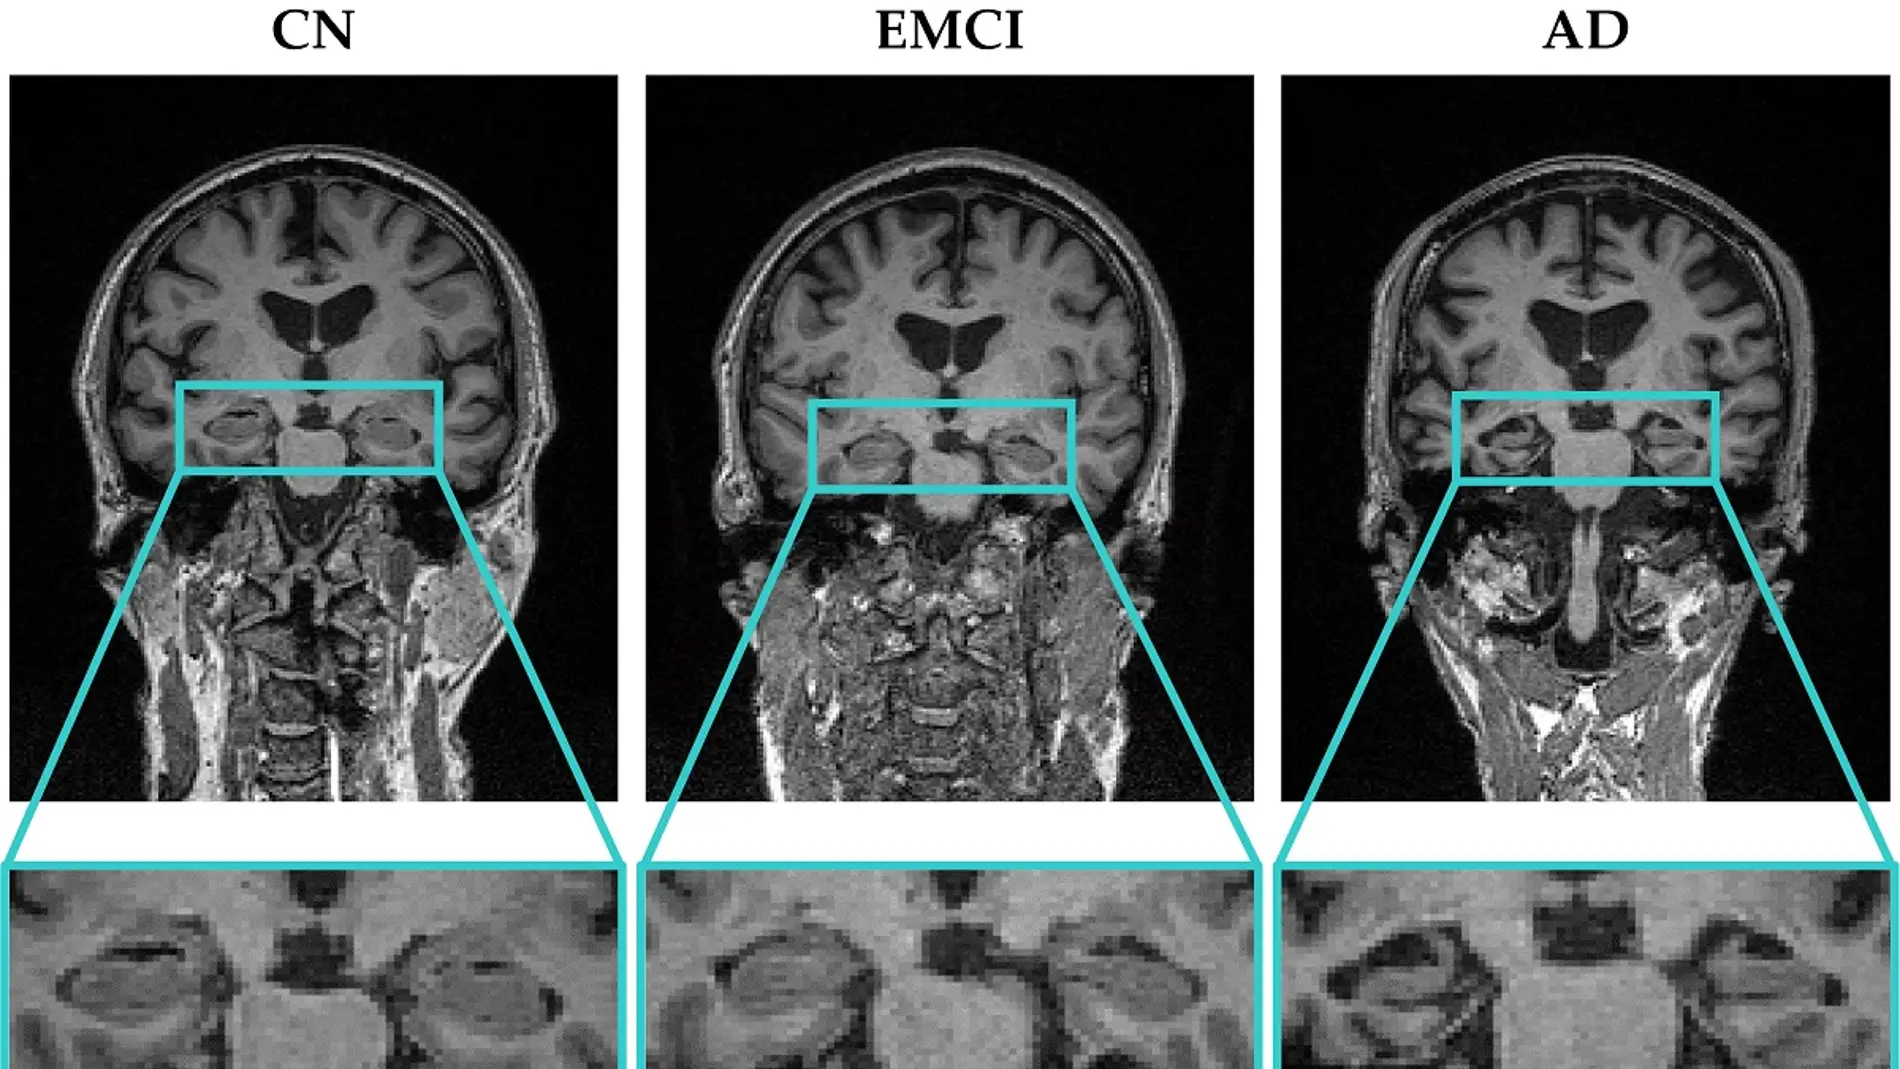

Para validar el nuevo software, los investigadores analizaron imágenes de resonancia magnética de tres grupos de personas: pacientes con alzhéimer, pacientes con deterioro cognitivo leve temprano y sujetos control. Los análisis fueron llevados a cabo en la región hipocampal (una de las regiones que más se ve afectada por la atrofia cerebral en las primeras fases de la enfermedad) usando regiones de interés circulares y esféricas.

El software desarrollado por los investigadores de la UPV realiza un procesamiento matemático de las imágenes, a partir del cual extrae unos parámetros que permiten cuantificar la homogeneidad o heterogeneidad de la región hipocampal. “Con estos parámetros podemos caracterizar y detectar en qué fase está la enfermedad y podemos ayudar a descubrir alteraciones imperceptibles a simple vista para los especialistas clínicos”, añade Rafael Ortiz, estudiante de doctorado de la UPV y uno de los desarrolladores del software junto a los estudiantes del Grado en Ingeniería Biomédica de la UPV, Carlos López y Carolina Giménez.